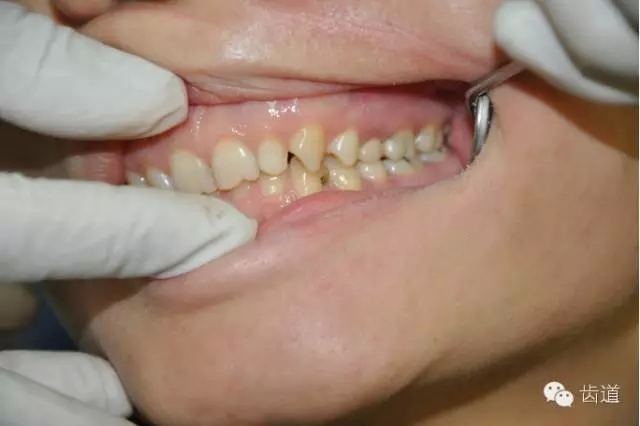

根據(jù)肩臺與牙齦位置不同可以分為3種:即齦上肩臺,齊齦肩臺,齦下肩臺

優(yōu)點(diǎn):最主要是邊緣隱蔽利于美觀——美觀性最好。常規(guī)用在前牙較多。

前牙的唇頰側(cè)

牙齒臨床冠高度偏低時,需制備齦下肩臺以提高固位性能 。(預(yù)備后前牙低于3mm,后牙低于4mm)